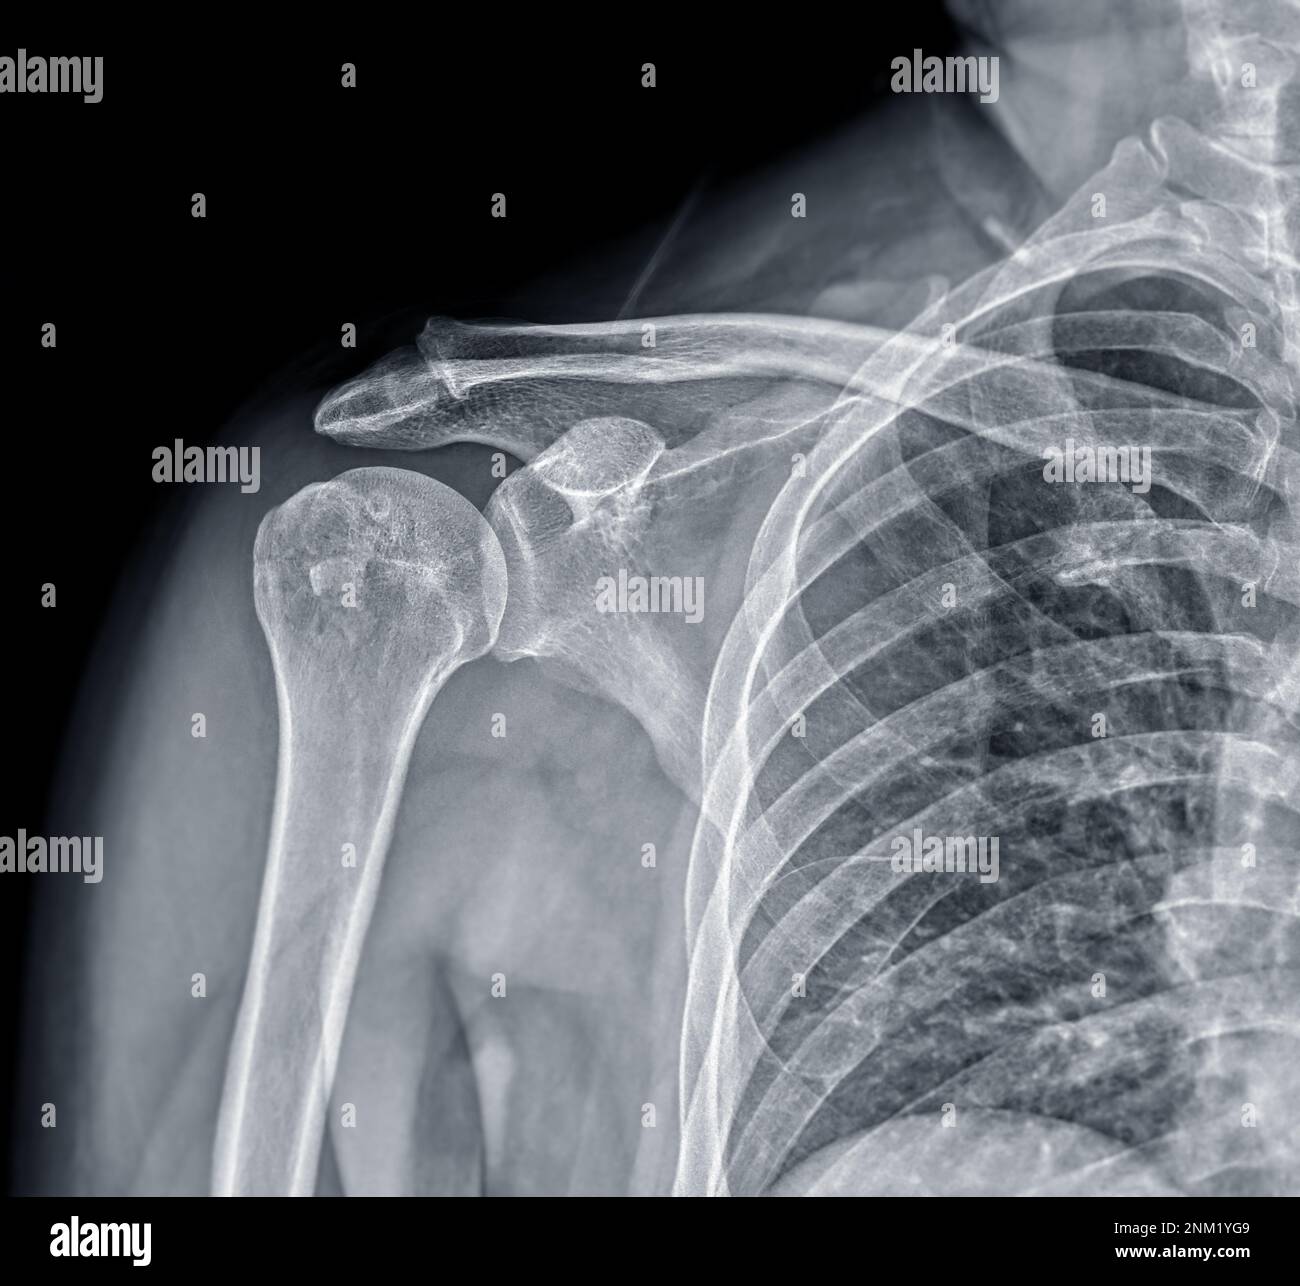

Shoulder Joint Fracture X Ray .   diagnosis is made with orthogonal radiographs of the shoulder. Articular surfaces should be parallel. The humeral head should be on the glenoid in any other. A patient with a proximal humerus fracture. Sometimes, additional imaging techniques, such as a.   the neer system divides the proximal humerus into four parts and considers not the fracture line, but the displacement as being significant in terms. Front and side pictures show the swelling and bruising down the arm.   in this review, we will discuss the mechanisms of injury, key imaging findings, therapeutic options and. Treatment with sling immobilization is indicated for minimally displaced. Magnetic resonance imaging (mri) :.

Magnetic resonance imaging (mri) :. Sometimes, additional imaging techniques, such as a. Treatment with sling immobilization is indicated for minimally displaced.   the neer system divides the proximal humerus into four parts and considers not the fracture line, but the displacement as being significant in terms. Front and side pictures show the swelling and bruising down the arm.   in this review, we will discuss the mechanisms of injury, key imaging findings, therapeutic options and. The humeral head should be on the glenoid in any other. A patient with a proximal humerus fracture.   diagnosis is made with orthogonal radiographs of the shoulder. Articular surfaces should be parallel.